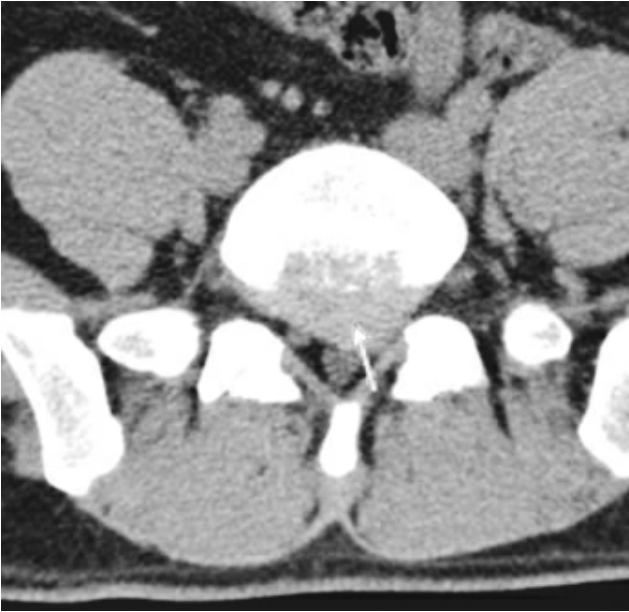

CT是将我们不能肉眼识别的软组织包括腰椎间盘,通过计算机对扫描数据的处理,变成能够被我们肉眼所识别的图像,它的成像技术可以显示骨骼和周围软组织,能清晰地显示纤维环是否破裂及髓核突出的位置,突出的程度,是否压迫脊髓和神经根,所以腰椎间盘突出症的病人要做CT,才能更好地了解突出情况(图21)。

图21 CT断层扫描下突出的椎间盘